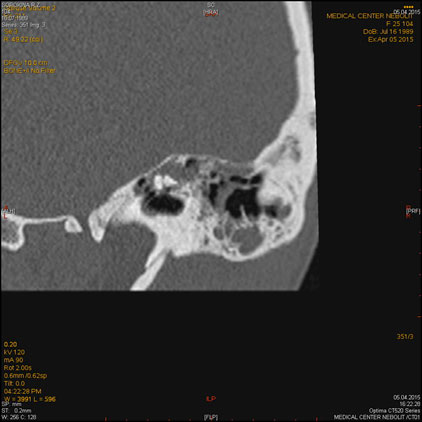

МСКТ височных костей

Показания:

- Воспалительные заболевания и их осложнения

- Травма, аномалии развития

- Опухолевый процесс